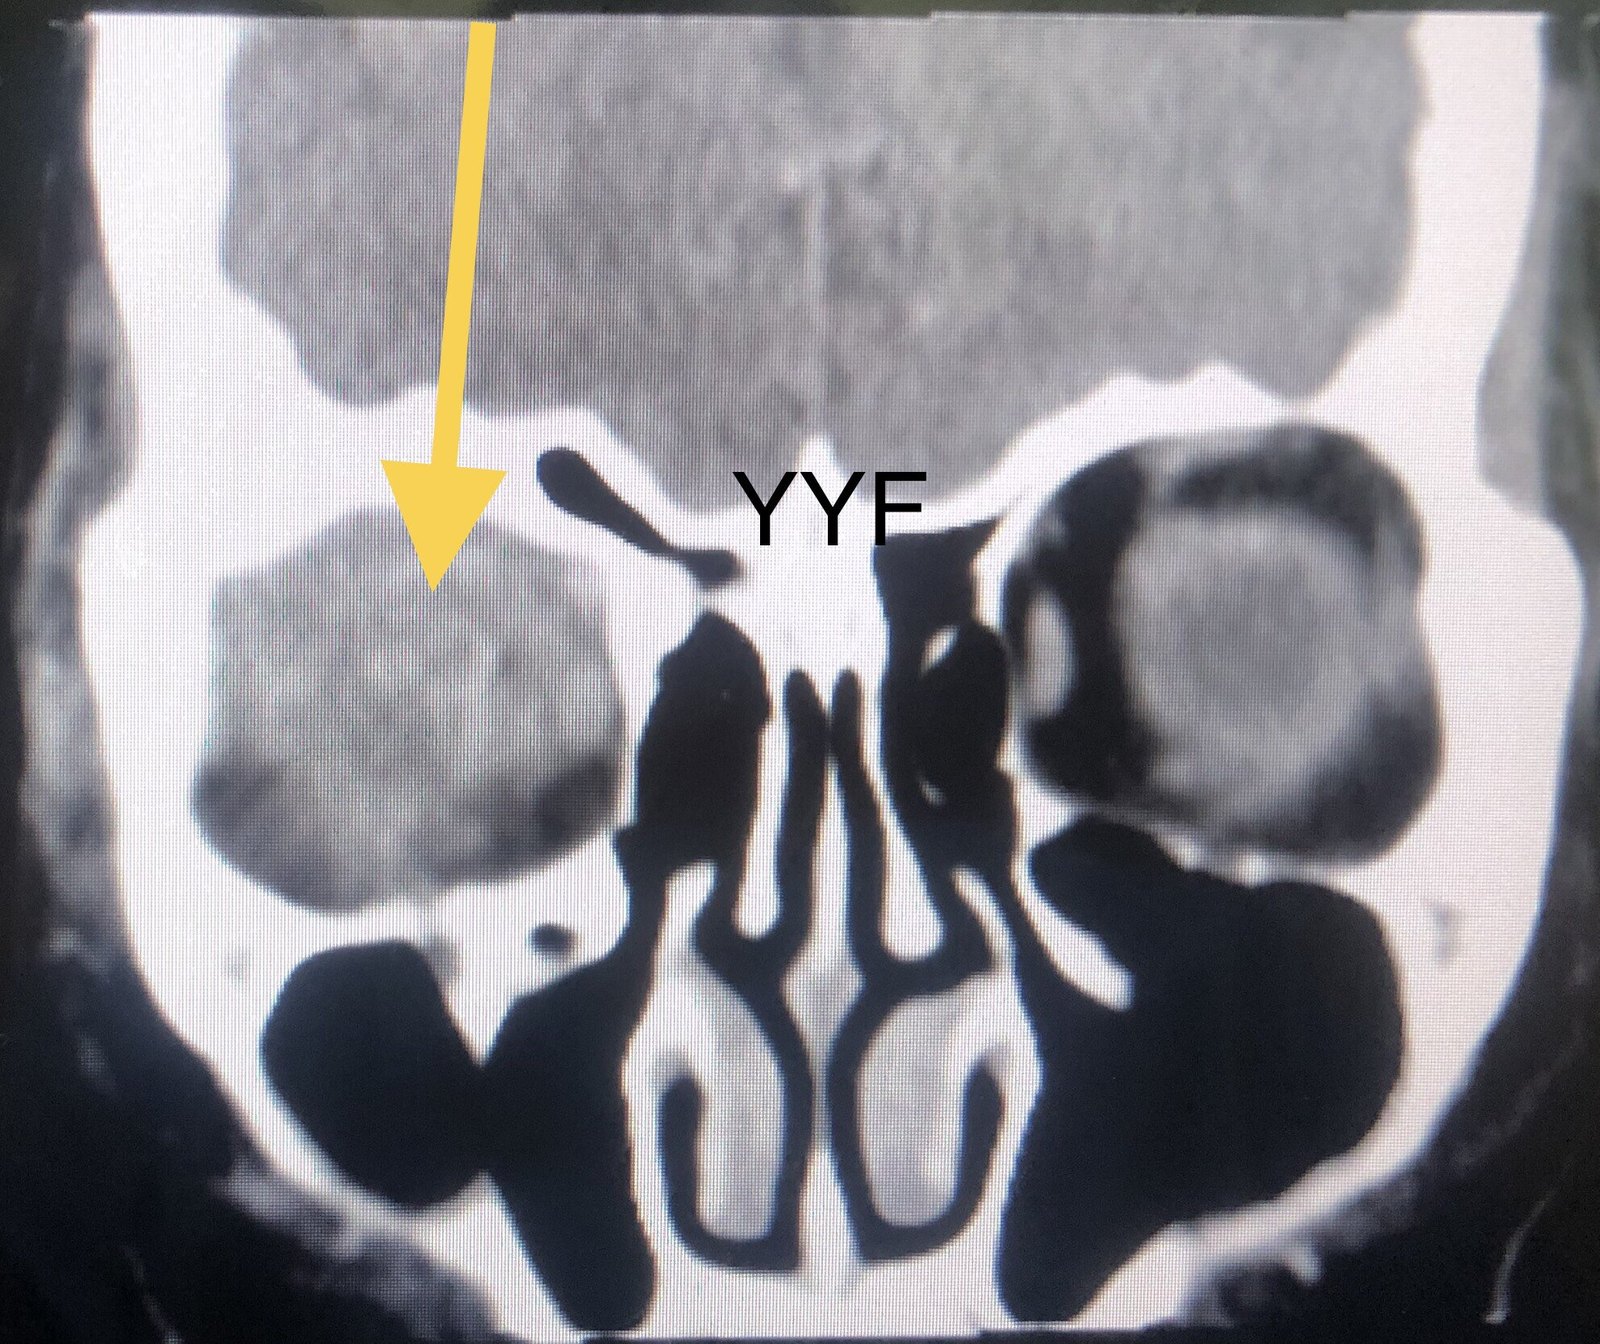

眼眶弥漫性占位

眼眶后段

本例病病变同样累及泪腺区,但远远超出泪腺范围,

病变累及泪腺区,但远超过